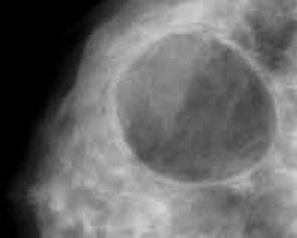

Кисты являются симптомами узловой формы мастопатии. Они образуются вследствие расширения одного из протоков молочной железы, сначала формируется капсула из соединительной ткани, ограничивающая полость, а потом в полости накапливается жидкость невоспалительного характера. По форме образования могут быть округлыми, овальными или иметь неправильную форму.

Размер кисты варьируется в диапазоне от нескольких миллиметров до 3-5 сантиметров. Практика маммологии подтверждает, что особо крупные в диаметре образования могут привести к деформации и изменению формы груди или к полному замещению ее ткани собой.

Киста средних размеров может быть обнаружена при пальпации, небольшие образования можно рассмотреть, проведя маммографию или УЗИ молочной железы. Если данные сомнительные, пациентам показано МРТ груди, однако используется этот метод редко.